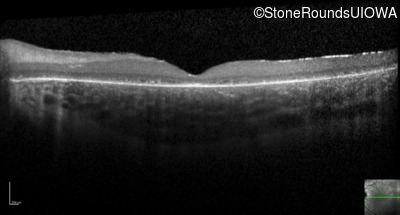

Optical Coherence Tomography - Left - 10/160 sc

Exemplar / OCT Stack